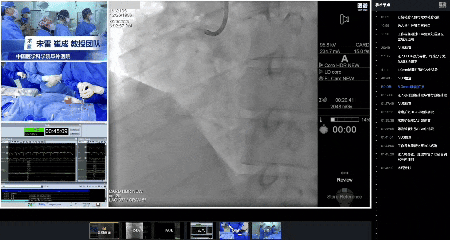

放置药物球囊

充分血栓抽吸后复查IVUS,提示第二转折处狭窄部位的低密度血栓已显著减少,局部血管直径为5.5 mm。考虑到该位置植入支架存在技术局限及潜在疗效不佳风险,经综合评估后决定采用药物球囊治疗。

由于右冠近段尚未处理,术者团队先使用4.0 mm普通球囊对右冠近段进行反复扩张,随后更换为4.5x35 mm药物球囊,在第二转折处实施反复扩张并成功释放药物球囊。术后IVUS检查显示真腔形成良好,附壁血栓进一步减少;冠状动脉造影证实第二转折处狭窄程度显著改善。手术顺利完成。

IVUS检查和最终造影